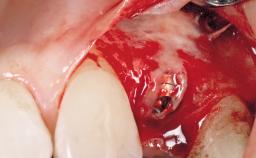

A 36-year-old female patient was referred for the replacement of the upper left central incisor (tooth 21), which had fractured. Although the tooth had been asymptomatic for many years, the crown began to loosen, at which time she presented to her dentist for an assessment. Teeth 21 and 22 had both been endodontically treated many years previously. She was a healthy individual and a non-smoker.

Bone Volume Deficient horizontally, requiring prior grafting